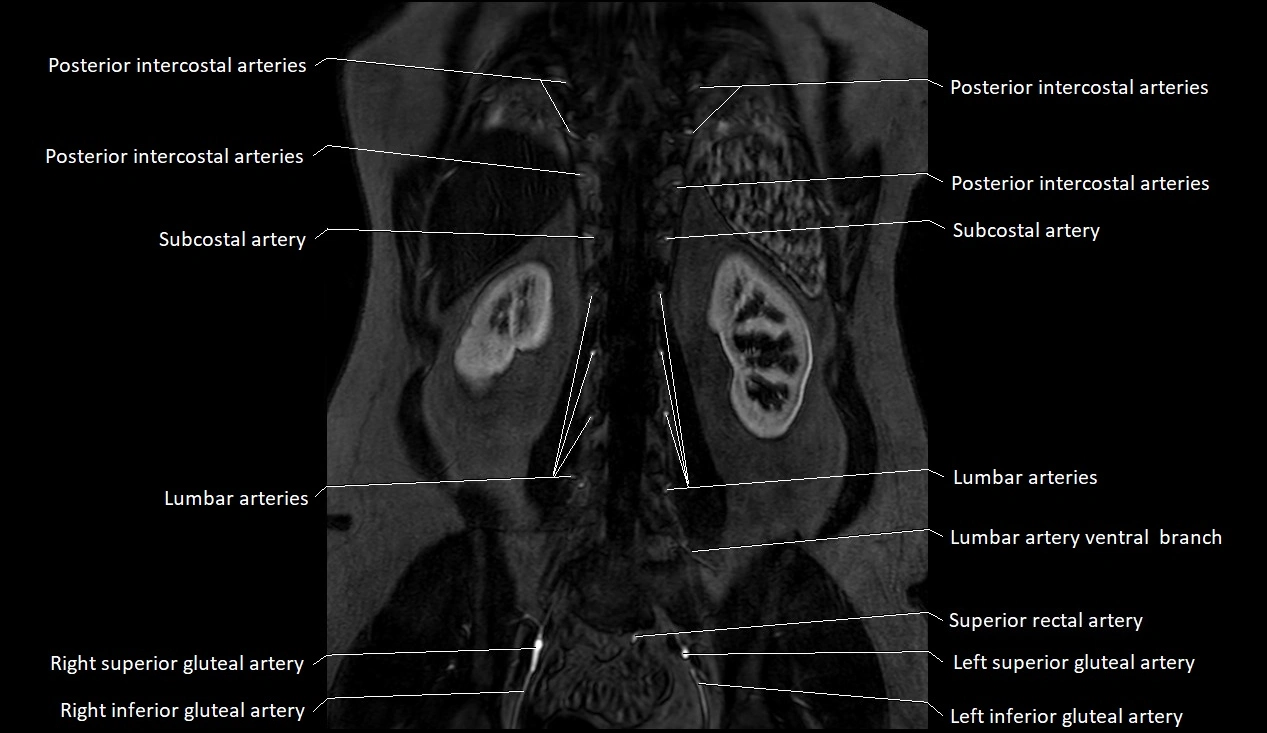

MRI images

image